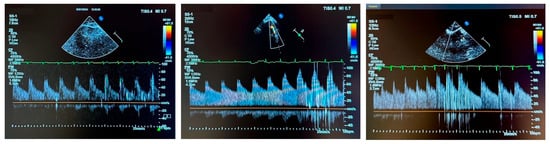

A 2 MHz sector transducer with color Doppler capability was used to locate the MCA at a depth of 3.5 to 4 cm from the skin, within the bone window between the lateral margin of the orbit and the ear, above the zygomatic arch. After identifying the appropriate location for the transducer, a contrast mixture (10 mL total, consisting of 8 mL 0.9% NaCl, 1 mL of the patient’s blood, and 1 mL of air) was prepared using 2 syringes connected to a 3-way stopcock. The patient was then instructed to perform a Valsalva maneuver [12]. The contrast was administered during the straining phase, 8 s after the onset of the Valsalva maneuver. The number of early HITS detected served as an indicator of residual leaks, and were classified according to ICC [12,13] in 4 categories: 1: No HITS (negative; no shunt), 2: 1–10 HITS (small shunt), 3: 11–25 HITS (medium shunt) and 4: >25 HITS, including the curtain feature (large shunt). Examples of ce-TCD are shown in Figure 2.

Figure 2. Examples of contrast-enhanced transcranial Doppler. Left Panel: ICC Category 2, Middle Panel: Category 3, Right Panel: Category 4.